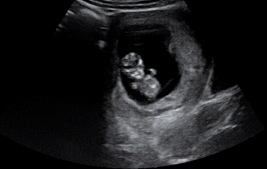

As we saw in the first section of this module, over the nine months of pregnancy numerous maternal experiences have the potential to impact fetal health outcomes. Although immature, the brain at birth has already been influenced by the environment that the growing fetus experienced. For example, teratogens, maternal stress and maternal malnourishment are some of the factors that can influence the developing brain of the fetus. Therefore, a discussion on healthy brain development must include ways to ensure pregnant people have healthy prenatal experiences. This is an important component towards providing a healthy foundation for societal health and well-being.

The following article from the National Scientific Council on the Developing Child provides valuable background information on the impact of early exposure to neurotoxins (substances that are toxic for brain development). Pages 10 – 12 outline important program and policy implications to reduce fetal exposure to neurotoxins and promote healthy brain growth before and after birth and during the early years of development.